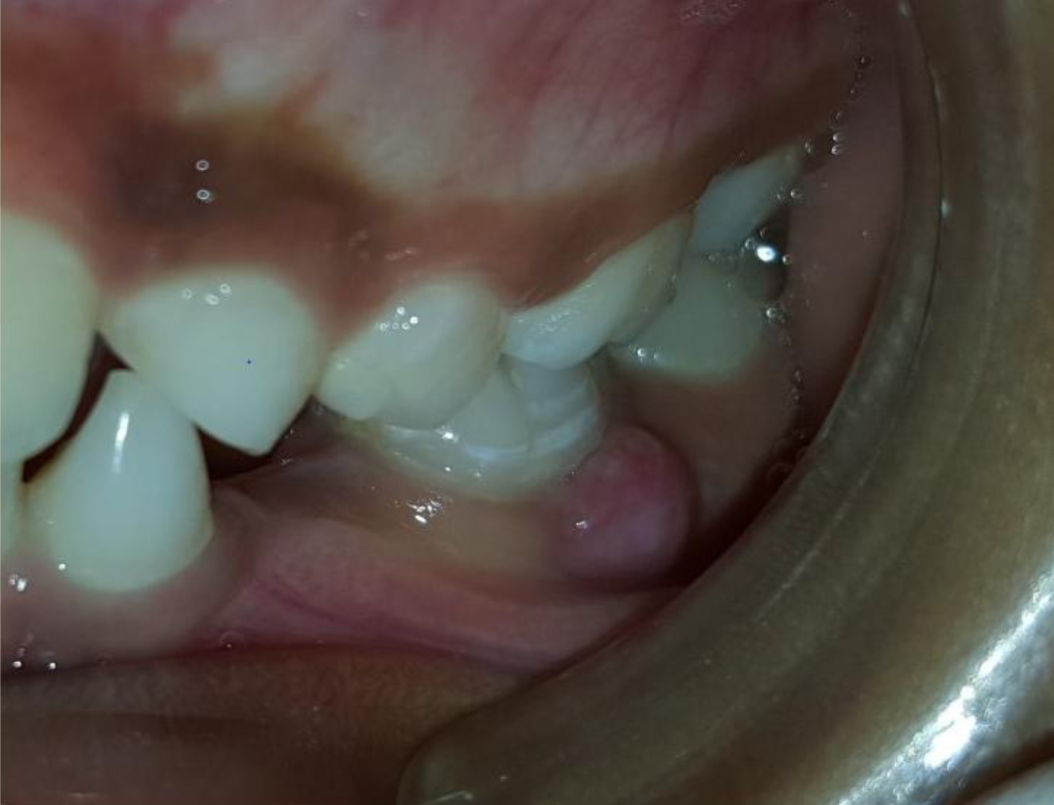

A nine year old boy reported to the Department of Pedodontics and Preventive Dentistry of Bharati Vidyapeeth Deemed University, Sangli with a chief complaint of pain and abscess in the lower left back region of the jaw since one month. Patient was a known case of autism spectrum disorder. He was inattentive, hyperactive and showed repetition of gestures. Psychological testing report showed childhood autism rating scale (CARS) 2, which falls into mild to moderate autistic category. Vineland social maturity scale (VSMS) measuring the social intelligence of child was found to be 31.5 with social age of around 5-6years. The family history was non-contributory. He was not on any medications and had reported no history of drug allergies. Extra-oral examination showed no specific findings (Figure 1). Intraoral examination revealed multiple carious lesions (Figure 2) (Figure 3). Occlusal caries involving enamel, dentin and pulp with 55 and 75. Intra oral dentoalveolar abscess was also seen in relation with 75 (Figure 4). Dentinal caries was seen with 85 and occlusal pit and fissure caries was seen with 65. No soft tissue abnormalities were appreciated. Radiographic evaluation by orthopantomogram was also done which revealed no abnormality (Figure 5). It was difficult for the patient to co-operate on the dental chair and understand the instructions given to him; hence treatment was planned under general anaesthesia. A complete pre anaesthetic evaluation was done and the patient was categorized under ASA II. Treatment plan was explained to the child’s parents and a written consent was obtained from them. The dental treatment done under general anaesthesia included pulpectomy of 55, 75 with glass ionomer cement restoration followed by placement of pre trimmed and pre contoured stainless steel crowns (Figure 6) (Figure 7). Glass ionomer cement restorations were done in 65 and 85 and pit and fissure sealants application on 16, 26, 36 and 46. Post-operative orthopantomogram showed well placed restorations and crowns (Figure 8). Patient’s post-operative recovery was uneventful. Treatment rendered reduced the pain and discomfort.Oral hygiene care instructions were given to the parents and maintenance protocol was explained and they were also encouraged for regular follow-up for preventive dental care. The two months follow-up revealed improved eating habits of the child.

Figure 4 Intra-oral dentoalveolar abscess in 75 region.

Figure 7 Stainless steel crown cemented on 75 and glass ionomer cement restoration on 85 and Sealants on 36, 46.